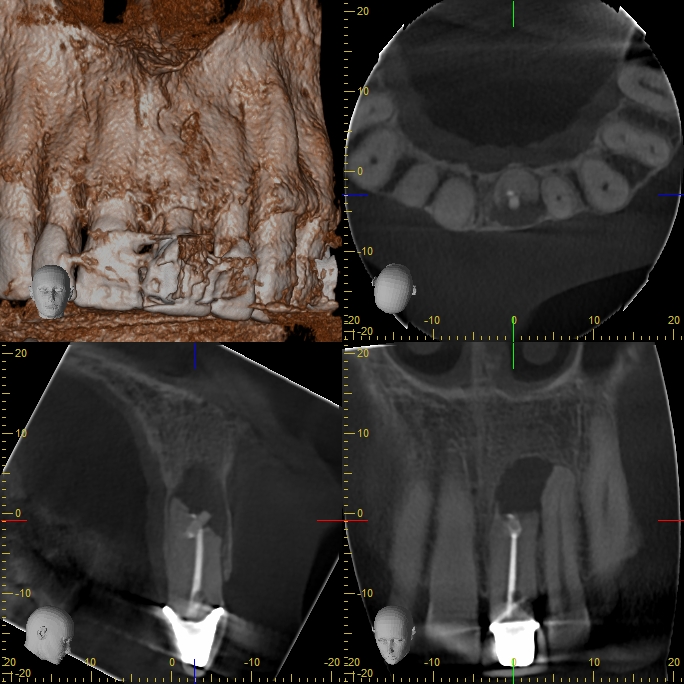

XYZView_20160615_185917

Unknown apical object (UAO)